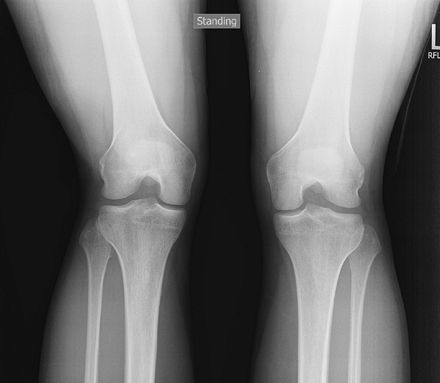

Leg Alignment—Include Joints from Hip to Ankle

Patient upright, equal weight in each foot. Both leg

alignment and leg length can be assessed on this study if

weight-bearing. The weight-bearing line passes from the middle of the

femoral head to the middle to the tibial plafond and should pass between

the tibial eminences. This determines varus or valgus deformity at the

knees. Used for pre- and postoperative assessment of total knee

arthroplasty.

![]() |

|

Figure 62 AP both legs.